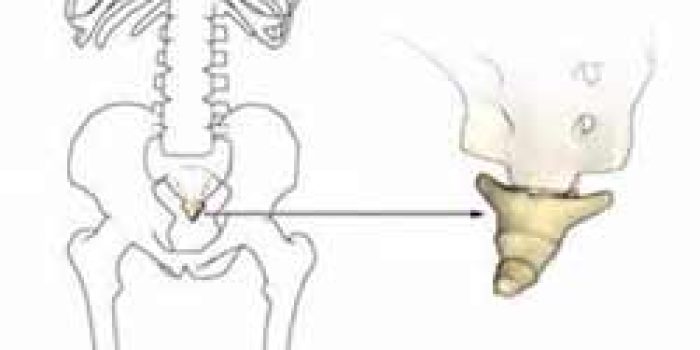

علت بسیاری از درد های دنبالچه نامعلوم است. بندرت ممکن است این درد به علت ضربه ( مانند زمین خوردن یا زایمان)، تحرک زیاد دنبالچه بوده و در موارد نادر عفونت، تومور یا شکستگی علت آن باشد. شیوع درد دنبالچه در زنان پنج برابر مردان است که به علت تفاوت شکل استخوان بندی لگن بین زنان و مردان می باشد.

نحوه درمان درد دنبالچه

درمان این بیماری در اغلب اوقات غیر جراحی است.

اگر بیمار چاق است کاهش وزن می تواند درد وی را کم کند

پزشک معالج معمولا برای کاهش درد و التهاب در ناحیه از داروهای ضد التهاب مانند پروفن استفاده می کند.

به بیمار توصیه می شود از بالشتک های مخصوص نرم یا بادی برای نشستن استفاده کند. در استفاده از این بالشتک ها باید دقت شود محل درد در وسط بالشتک قرار گیرد تا فشار مستقیمی به استخوان دنبالچه وارد نشود.

بیمار باید از نشستن در محل های سرد اجتناب کند. گرم کردن محل درد در بسیاری اوقات شدت درد را کاهش می دهد.

گاهی اوقات فیزیوتراپی بصورت استفاده از گرمای موضعی و یا اولتراسوند میتواند به بهبودی بیمار کمک کند.

در مواردی که درد بیمار به درمان های معمول جواب نمی دهد ممکن است نیاز به عمل جراحی وجود داشته باشد